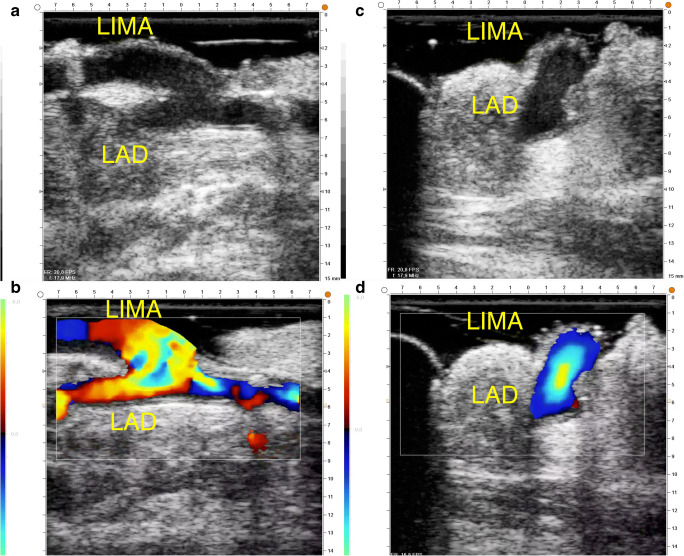

In off-pump procedure, the scan of the anastomosis should be done during stabilization of the vessel to avoid motion artifacts and obtain good quality imaging. In on-pump CABG, for free-graft, the scan should be performed by gently injecting the conduit with blood. The proximal anastomosis itself should be scanned (Fig. 3). In case of arterial conduit, the temporary opening of the graft permits to obtain adequate imaging. The anastomosis should be checked in both long- and cross-sectional views with 2-D and color flow mapping (Fig. 4). To obtain good acoustic coupling, a sterile gel can be used or the pericardium can be filled with saline solution. For TTFM, the flow meter should be connected to patient’s EKG and blood pressure in order to obtain reliable measurements, especially for the parameter DF. The measurement is obtained after the completion of anastomosis with the heart in normal position in off-pump surgery, after aortic cross-clamp release in on-pump surgery and weaning from cardiopulmonary bypass. The last measurement should be done after heparin reversal before chest closure either in off- or on-pump CABG. The technical aspects to obtain reliable TTFM measurements are related to avoid any compression of the graft with a too small a probe (use probe with adequate caliber), obtain good acoustic coupling using the gel, measure as close as possible to the anastomosis, and avoid vessel kinking.

Fig. 4.

HR-ECUS of a left internal mammary artery to LAD. a 2-D longitudinal view. b CFM longitudinal view. c 2-D short axis view. d CFM short axis view

We developed a flow chart of intraoperative verification to guide the surgeon through the entire procedure of graft assessment [13]. The first step of intraoperative graft verification procedure is the check with HR-ECUS of the arterial conduit. Subsequently, after the completion of the distal anastomosis, the second step is the morphological verification with HR-ECUS. In case of stenosis, the anastomosis should be redone immediately. The third step is the functional verification of the graft with TTFM. Repeated measures should be obtained as indicated in the previous section. There are three possible scenarios. The first (low MGF, low PI, and BF between 0 and 3) indicates a graft with a poor run-off. If the parameters will improve after dobutamine test, we can argue that the graft will have a good fate, conversely the risk of graft failure is high (Fig. 4). The second scenario (low MGF, high PI, and high BF) is a situation of competition of flow. This situation can occur in case of a graft put on a vessel with a moderate stenosis or more commonly in case of composite arterial conduits when the stenoses of the native vessels are unbalanced. If the parameter values will improve after dobutamine test, the graft will have a good prognosis, conversely especially for composite grafts; conduit configuration should be rearranged.